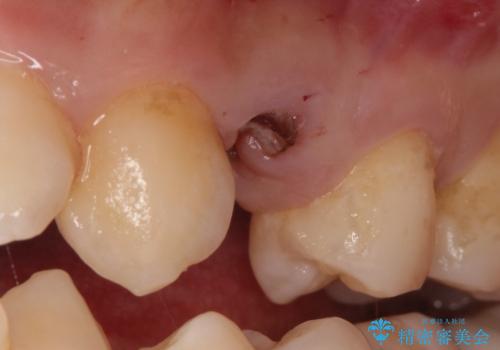

歯を保存するのは出来ないと診断し抜歯した後にインプラントで治療を行いました。

長い間虫歯を放置していたため、根っこだけになっている状態でした。このままでは被せ物を被せられないため抜歯を行い治癒を待った後にインプラントを埋入しオールセラミッククラウンで治療を行いました。